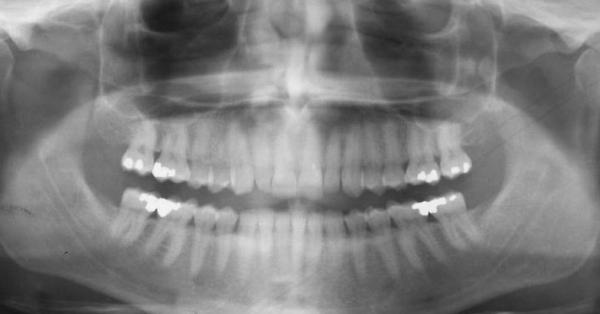

В первую очередь врач устанавливает наличие симптомов, проводит осмотр полости рта, изучает анамнез. В некоторой степени это помогает установить причину данного состояния и установить форму, стадию заболевания.

Также проводятся следующие методы диагностики:

- Изучение симметрии, пропорциональности, внешний осмотр. Необходимы для анализа степени разрушения, уровня стертости, состояния твердых и мягких тканей, выявление осложнений и определения метод лечения.

- Электромиография. Назначается с целью исследования жевательных мышц.

- Обследование височного и нижнечелюстного суставов. Помогает становить наличие различных сопутствующих патологий.

- Электроодонтодиагностика. Показана при установлении второй и третье степени стираемости. Проводится с целью выявления наличия незатронутой пульпы.

Правильно установить диагноз помогает только комплексная диагностика. На основе данных различных исследований врач устанавливает степень, формы и тип заболевания, а также определяет схему лечения.